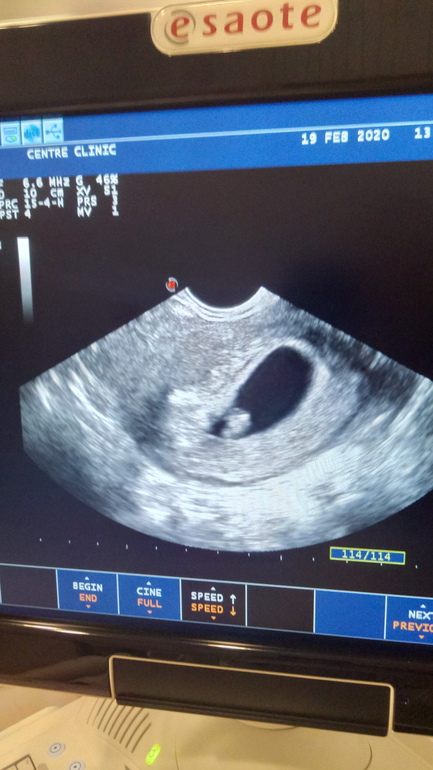

Второе УЗИ 19.02.2020, срок беременности по М 7+6. Второй эмбрион так и не нашли, но ПЯ и желточный мешочек очень большие.

Кистозное изменения не слишком хорошо.Просто наблюдать нужно за яичником.Судя по второму узи уже все нормально.На мой дилетантский форумный взгляд беременность нормально развивается, срок 7 недель по КТР отлично все, сб хорошее.

Сейчас специально залезла в цифры: у вас плодное яйцо соответствует промежутку 8-11 недель.

У врача спрашивала - это вполне норма. Главное, чтоб не маленькое было.